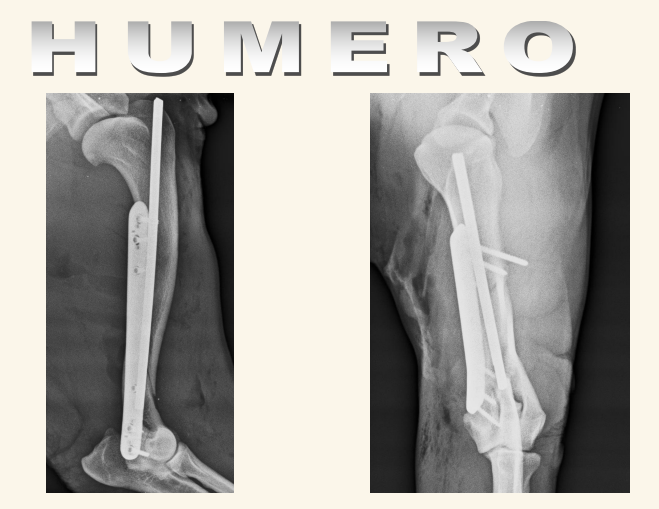

Humero:

Fracturas es lo mas comun, sobre todo en espiral. Pueden tener lesiones neuronales recuperables

Los sarcomas aparecen lejos del codo en extermidades anteriores y cerca de la rodilla en extermidades posteriores.

Las neoplasias sueln ser en la zona proximal del humero